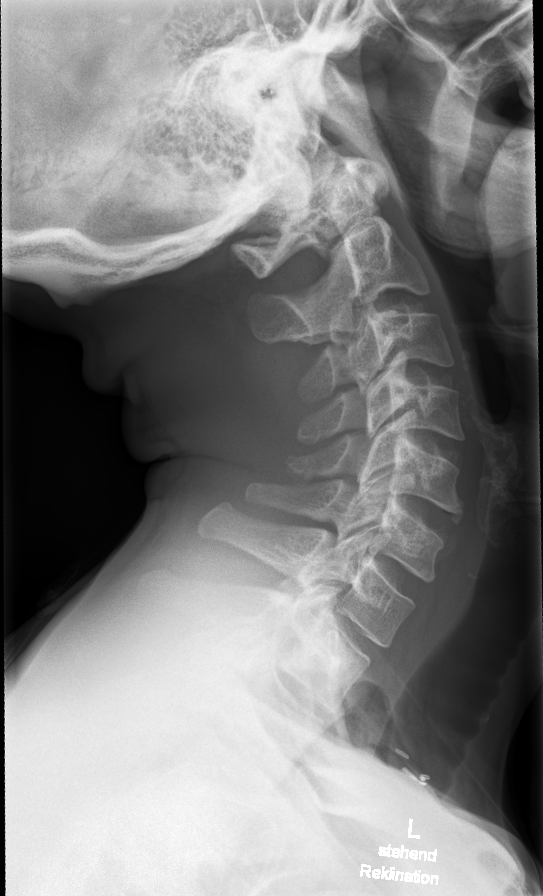

HWS Reklination im Röntgen

Abbildung einer reklinierten Halswirbelsäule im lateralen Röntgenbild.